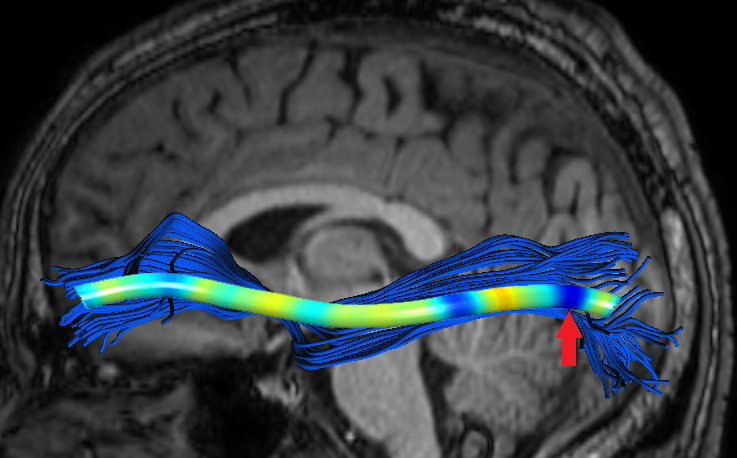

Experiments also showed significant FFDD longitudinal changes between mid-season and post-season scans in some football players. Fig. 7 presents mid- and post-season MD-FFDD profiles comparison of the left IFOF of one of the players, showing increased irregularities over time at the occipital part of the tract. Fig. 8 presents a similar MD-FFDD longitudinal analysis of the FMT of a different player, showing increased irregularities at the central part of the tract.

| Mid vs. Post | Mid-season | Post-season | ||

|---|---|---|---|---|

![]() |

|

STDs |